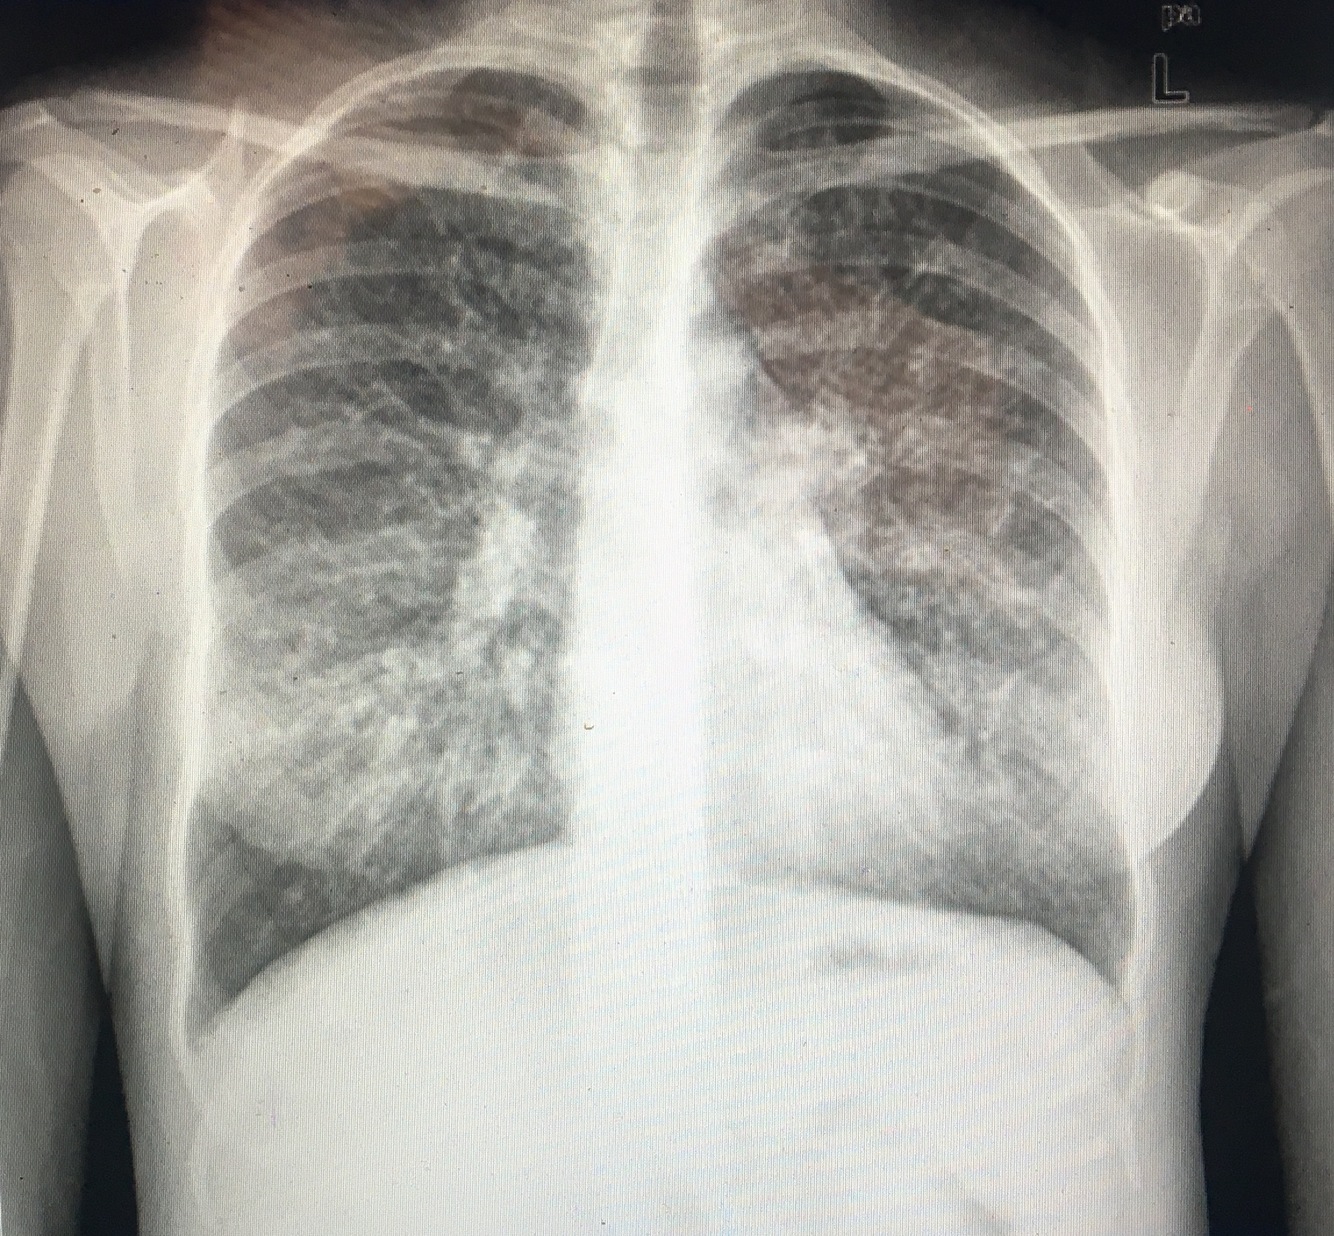

What’s the most significant finding in this CXR and what does it indicate?

Westermark Sign! = Pulmonary Embolus!